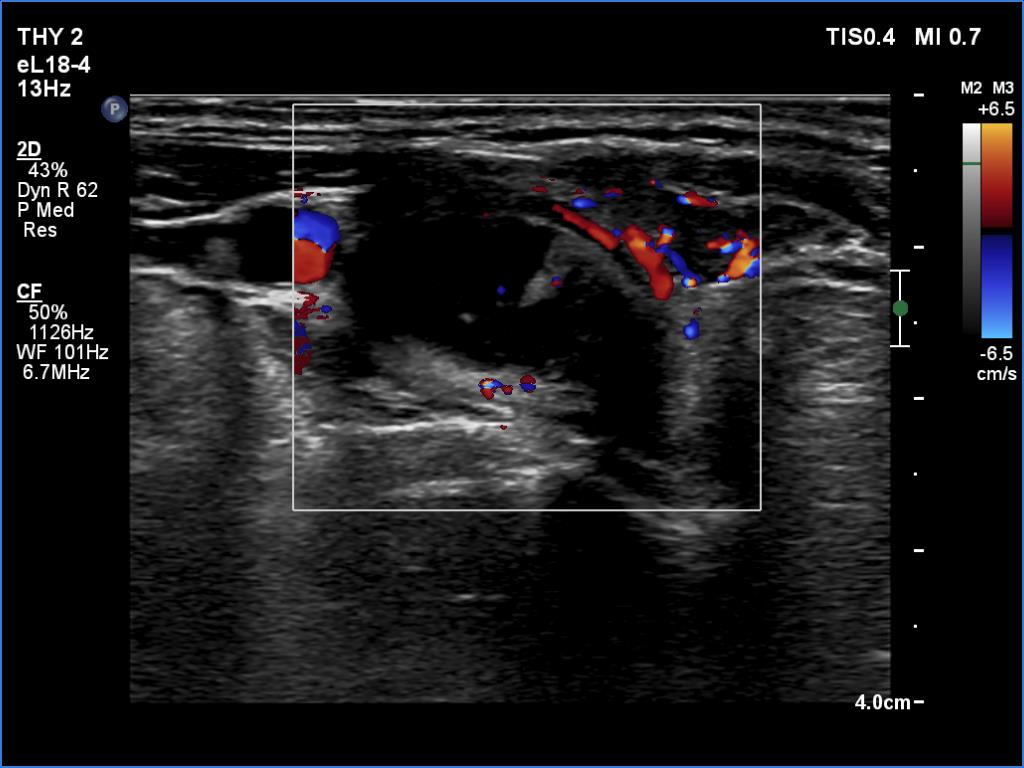

Ultrasonography. The thyroid was hypoechoic and presented several more hypoechoic and echonormal islets corresponding to the underlying thyroiditis. There was a mixed, dominantly cystic mass dorsal to the lower two-third of the right lobe. The lesion has echonormal solid part and showed intracystic echogenic figures.